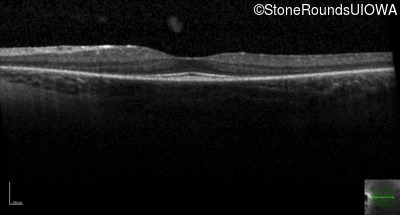

Age at visit: 19 years (Visit 2)

The clinical features favoring the diagnosis of retinitis pigmentosa with anisocytosis include: childhood onset periodic fever; mild anemia; anisocytosis on peripheral blood smear; night blindness and constricted visual fields as his earliest visual symptoms; bone-spicule-like pigmentation and narrowed arterioles on fundus examination; loss of outer retinal structures on OCT; and, normally sighted parents.